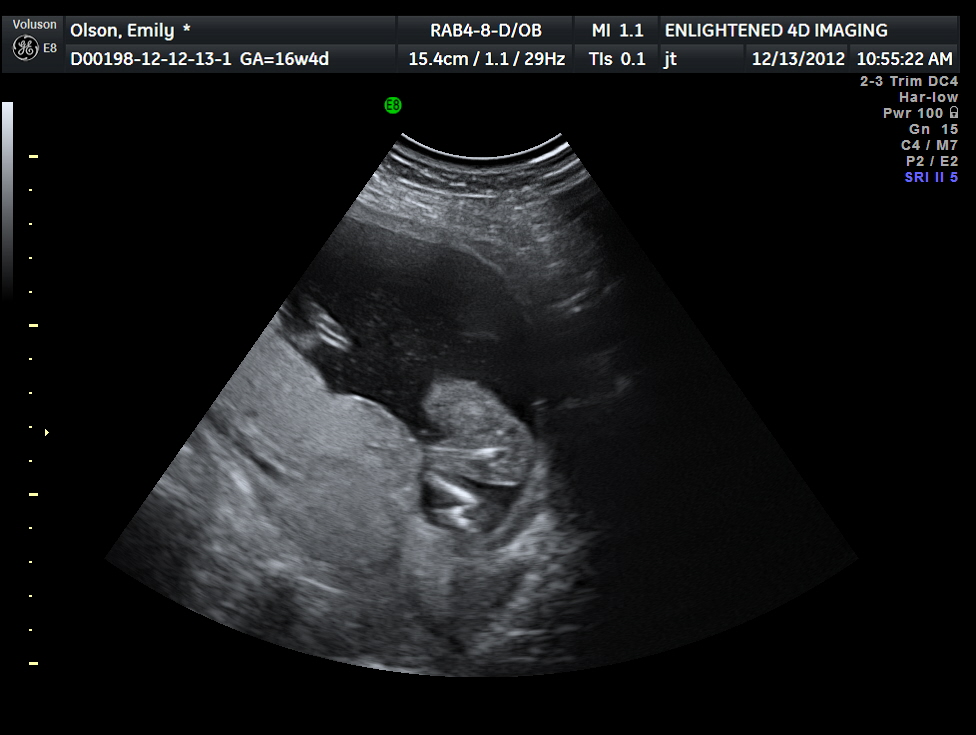

Anyways, when we got there Nikki took little video clips of everyone talking to the baby and saying what our gender predictions were. I am really excited to see those videos and I am really glad that we are doing little things during this pregnancy that we can look back on and smile and have something to show for it. The ultra sound tech got there and led us back to the room. It was a huge room with couches and a big projection screen that we would see the ultrasound on. Everyone got all situated, I got the blue goo on my belly and we began the ultrasound. Right away you could see baby up on the screen heart beating super strong, the tech was moving the wand all over my belly trying to get different shots of baby. Well, baby wasn't budging, and I'm thinking, OH GREAT the baby's gunna be stubborn again! After a couple of minutes of me flipping on my side and upside down and doing backflips.... (okay maybe not the last two...) he showed us how the baby was sitting in a pocket in my uterus (that sounds really weird and gross!) and she was all comfy and didn't want to move. Wellll then he gets up and asks me if I like chocolate and I'm like DUH! I'm pregnant and I am a woman of course I like chocolate! So he disappears and comes back with a Lindor Truffle. Within 1 minute the baby's heart rate went up and the baby started kicking and flipping and moved to the complete opposite side of my uterus! It was the most amazing thing I have ever experienced, he showed us all the fingers and toes and legs and arms and heart and spine and explained all these different facts to us. I couldn't look away from that screen, before my eyes was the most amazing little human being, moving and kicking and raising its arms, and this little human was mine, with my DNA inside it's little body. It was so SURREAL.

| All cozy in the pocket! |

The tech almost right off the bat had an idea of what the gender was, he kept saying that his prediction was very consistant with what he was seeing, and of course we were all dying to know!! Its so funny because before the ultrasound my mom thought the baby was going to be a girl and then she said she had a dream it was going to be a boy and then the whole ultra sound mom kept calling the baby a "he," I kept saying "OR SHE," I had a feeling the whole time that it was a girl. Finally the tech said, "okay guys, you want to know what you're having?!" and of course by this point my mom and Nikki are pretty much a foot from the screen eyes and video cameras glued to it! He went through showing us what we were looking at and talking about what these parts of the body were and what they were doing and then he said, "So that means, GIRL!" My jaw literally dropped, my mouth was wide open for 5 minutes, I was laughing and crying and these emotions just flooded over me of complete joy and peace. I was having a baby girl, I knew it all along, but that very moment just confirmed everything. It was one of the most precious moments of my life.

| Its a GIRL! |